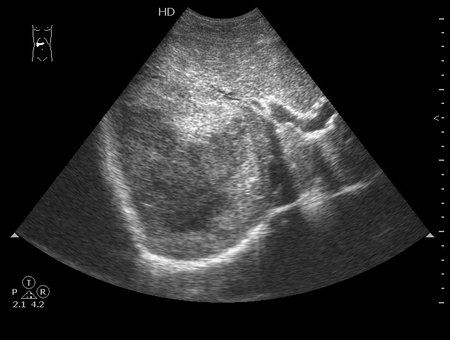

Молодой человек, наркоман, поступил в хирургическое отделение с подозрением на абсцесс печени.

Жалобы на высокую температуру, слабость.

Сонограмма печени:

Год назад при УЗИ в печени находили образование больших размеров.

Что-то не укладывается именно ультразвуковая картирка в абсцесс печени.

на узи на абсцесс не похоже, образование солидное ----гепатома?

Гигантская капилярная гемангиома печени.